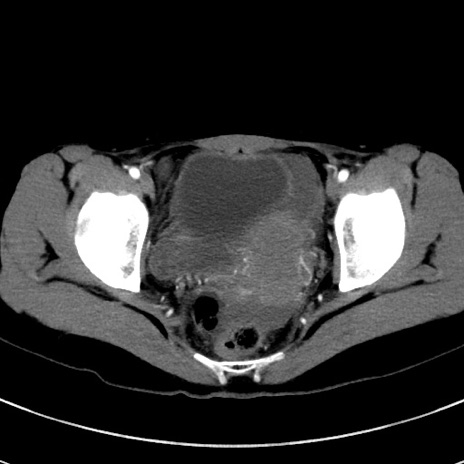

症例17(横断像)

【症例】20歳代女性

【主訴】嘔吐、下腹部痛

【現病歴】昨日夕食後に嘔吐し下腹部痛が出現。本日になっても嘔吐持続し改善しないため来院。

【身体所見】意識清明、BT 37.2℃、BP 108/67mmHg、腹部:平坦、やや硬、下腹部正中から右にかけて圧痛あり、反跳痛軽度あり、tapping pain(+)。

【データ】WBC 13600、CRP 14.94